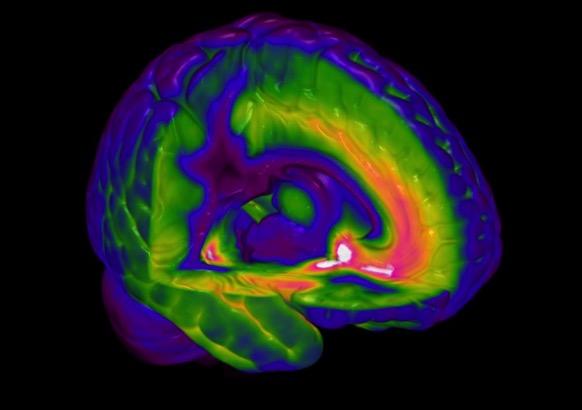

Fig. 1

A PET scan of a GABA-A receptor subtype [the alpha5]

PET = positron emission tomography and its close cousin of SPECT = single photon emission computerised tomography – are used to explore brain activity and drug binding and thereby receptor localization.

These techniques use radiolabelled tracers such as 11Carbon or 18Flourine for PET or 99Technecium metastable (99Tcm) or 123Iodine for SPECT. These unstable radionuclides decompose in the brain giving out 2 gamma rays in the case of PET or a single photon in the case of SPECT and these electromagnetic rays are detected by sensitive photocells arrange in a ring around the head. These techniques can be used to explore changes in either blood flow [eg with 15O water or 99TmHMPAO] or in cellular metabolic activity [using the uptake of 18F-deoxyglucose that enters cells in proportion to the usage of glucose in them].

In some cases it is possible to attach a radioactive nuclide to a drug and so measure its entry and distribution in the brain. If the drug has high affinity for a receptor/reuptake site/enzyme then the density of these can be estimated in discrete brain regions from the radioactive signal in each – fig 1. Currently we have good tracers for estimating the density of a number of receptors for the dopamine 5-HT and GABA-A systems; these are described in more detail in part 2. The time resolution of the PET/SPECT signal is in the order of minutes.